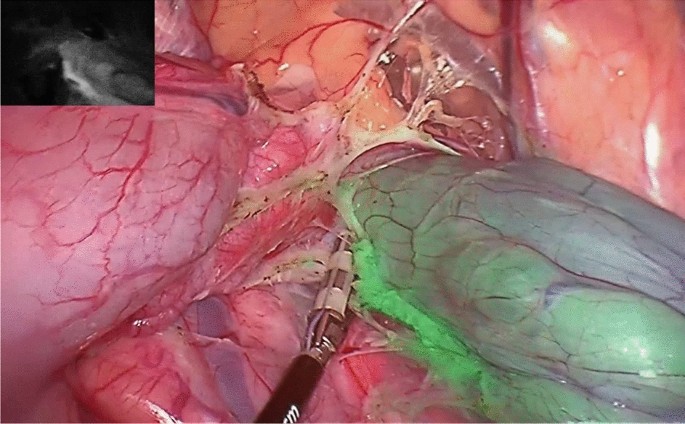

Sometimes, instead of chemo and radiation, a more extensive surgery, such as low anterior resection (lar). Most patients with rectal cancer undergo surgery about eight weeks after finishing chemotherapy and/or radiation therapy. Preoperative local staging with a rectal mri is mandatory in all patients with a diagnosis of rectal cancer, complemented by erus especially in the evaluation of early rectal lesions, where it may be superior to mri[20].